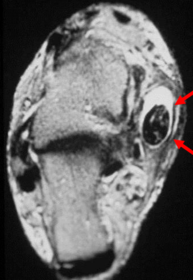

What does this indicate? | Increased signal and enhancement of the soft tissue plantar to the proximal phalanx suggestive of subcutaneous infection without abscess |